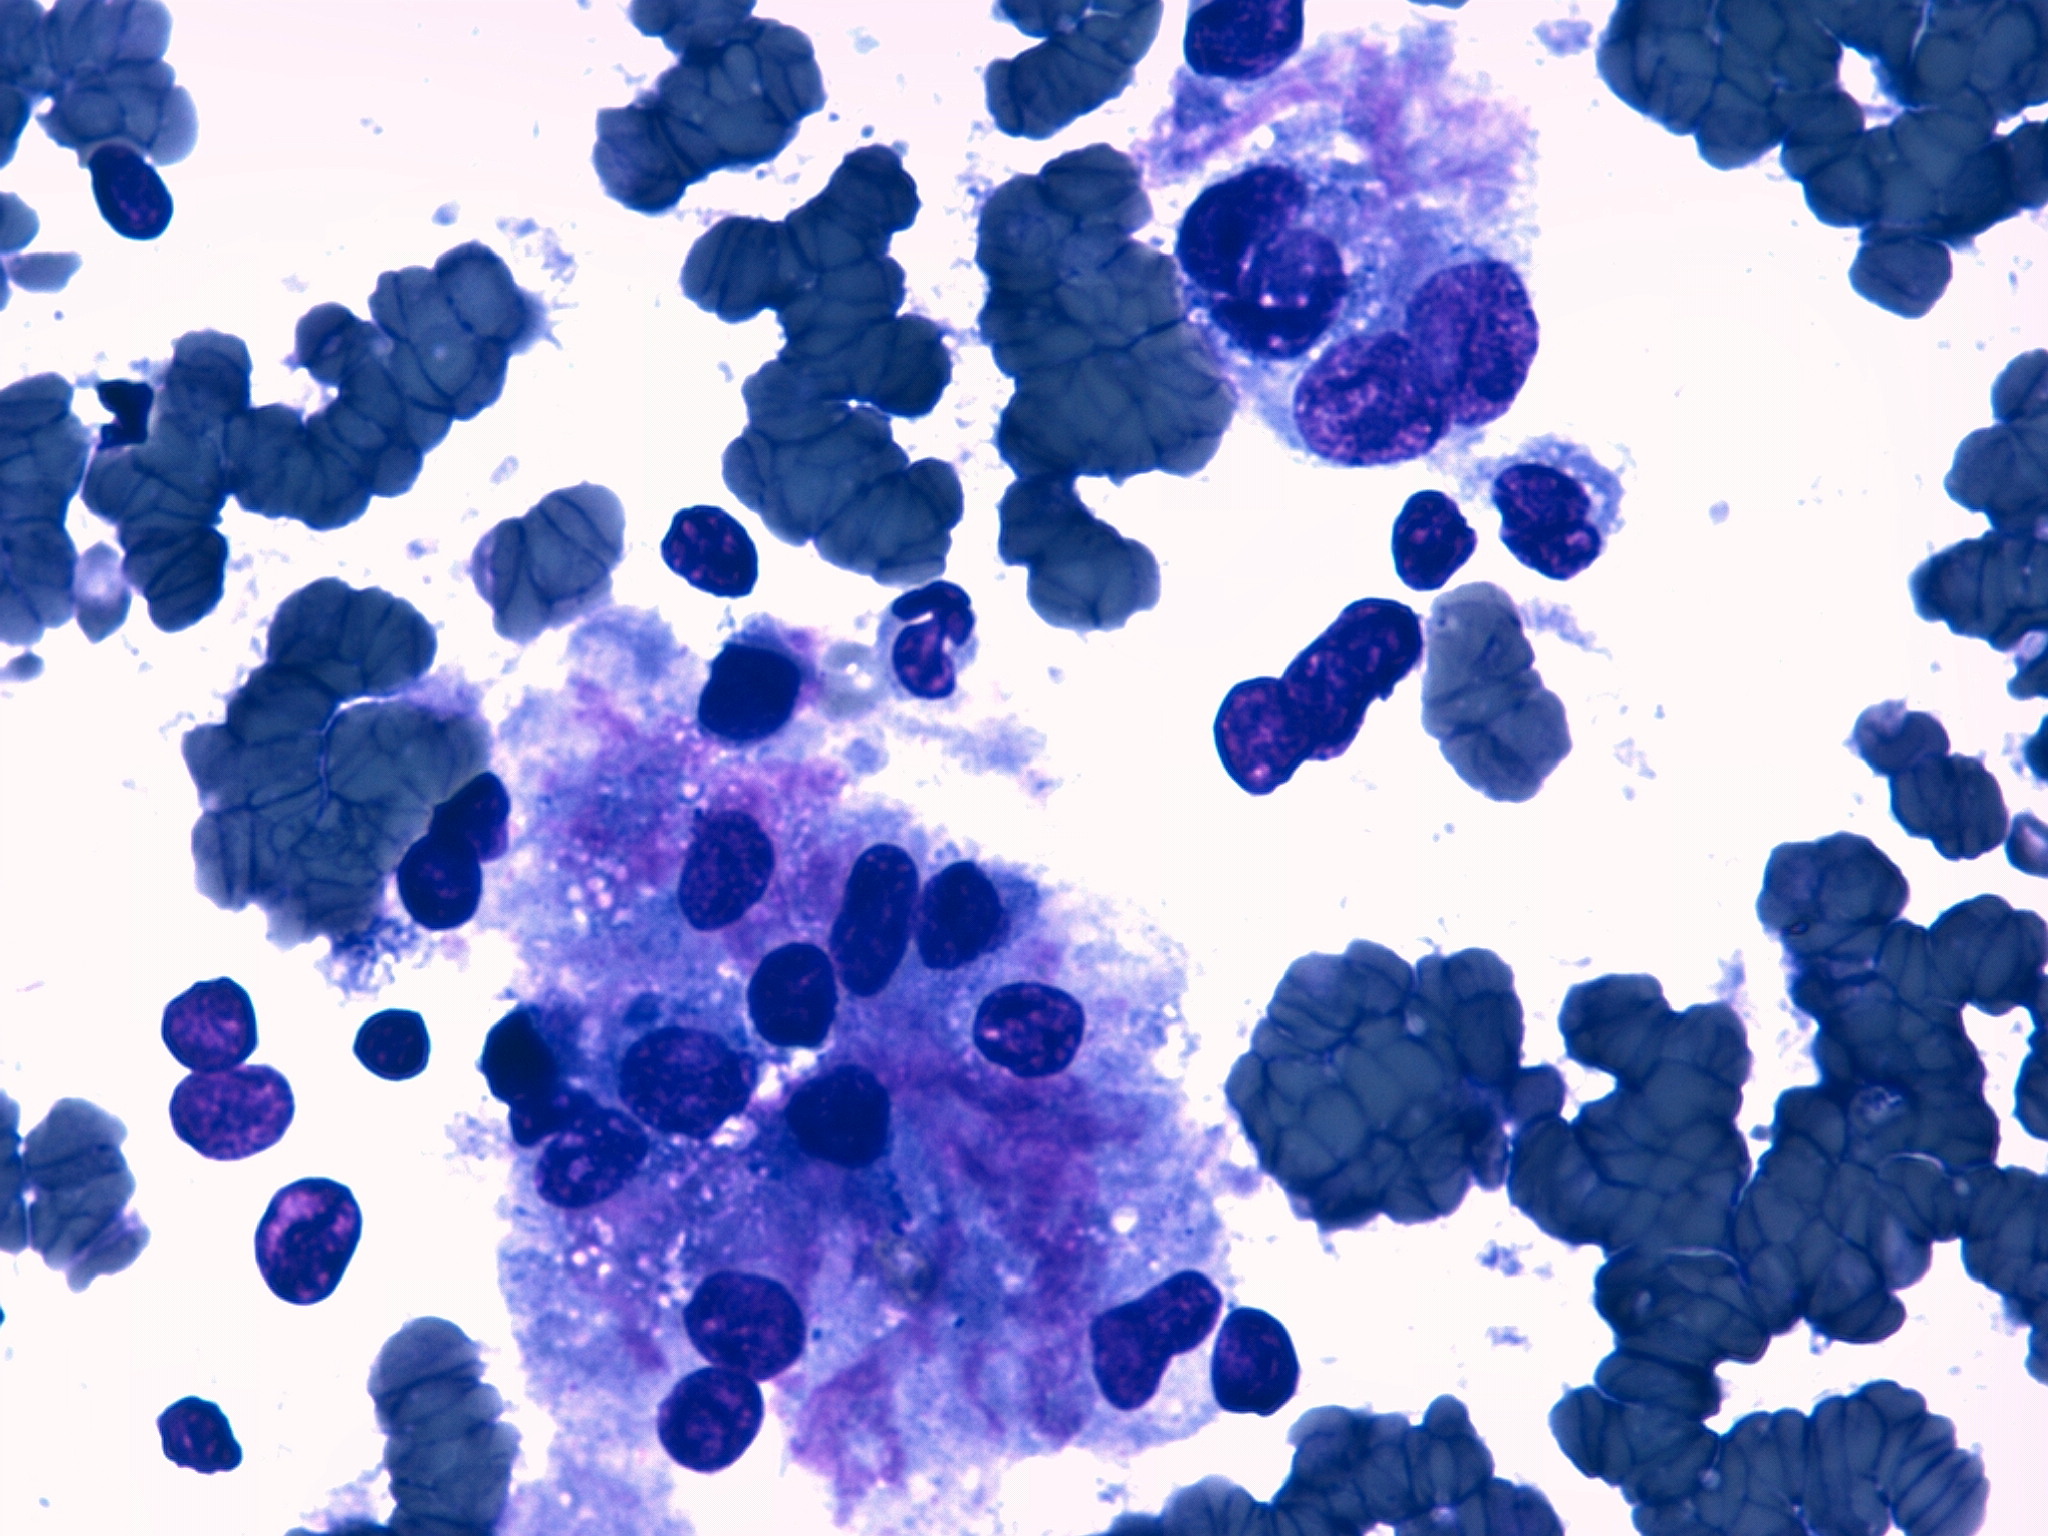

Dr. Alberto Gallardo (patòleg) i Dra. Ferrer (radiòleg).

Clínica Girona

Paciente varón de 54 años con tumoración en unión de cuadrantes superiores de mama izquierda que parece depender del músculo. Se realiza punción con aguja fina.

Se adjunta fotografías de las extensiones, bloque celular y mamografía y ecografía.